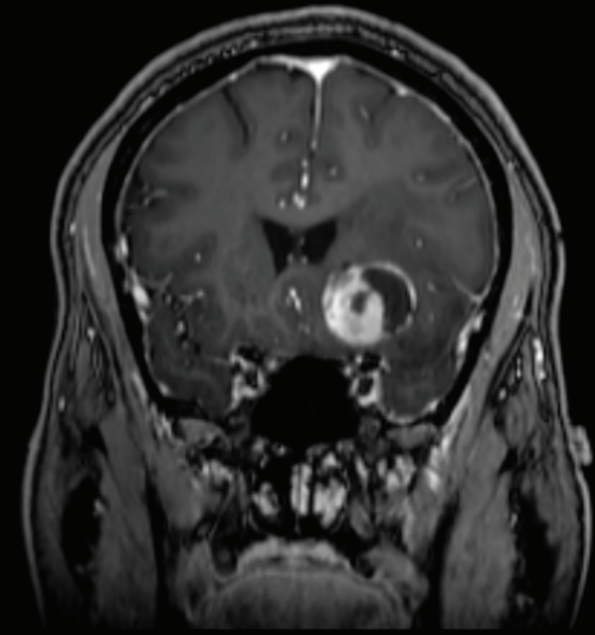

冠状面T1造影后磁共振成像显示左侧额叶囊肿性增强病灶。可见肿瘤与周围脑实质的清晰轮廓。